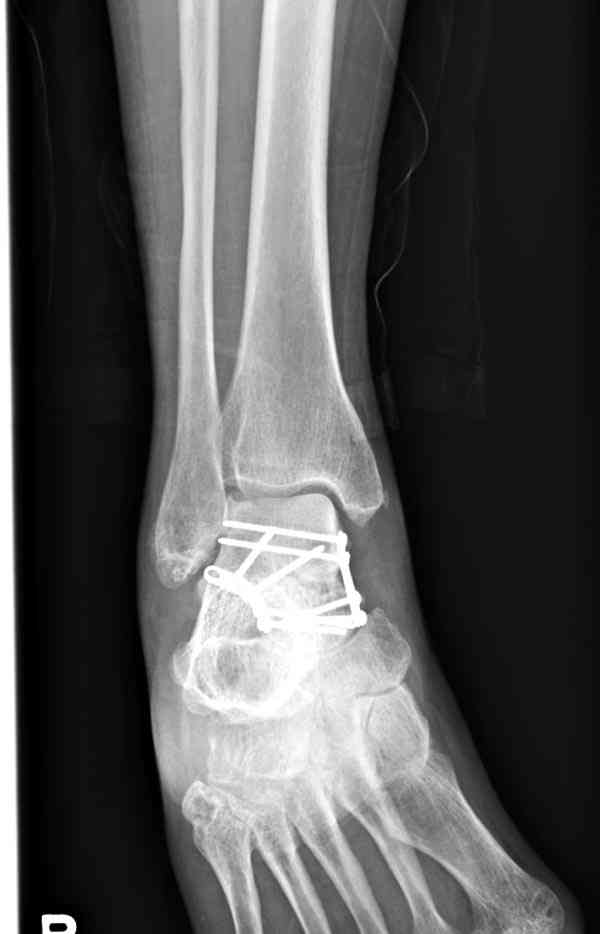

Случай с множественным оскольчатым переломом тарана оперированный из двойного доступа.

Через 2 мес.:

Через 8 мес.:

Через 14 мес.: